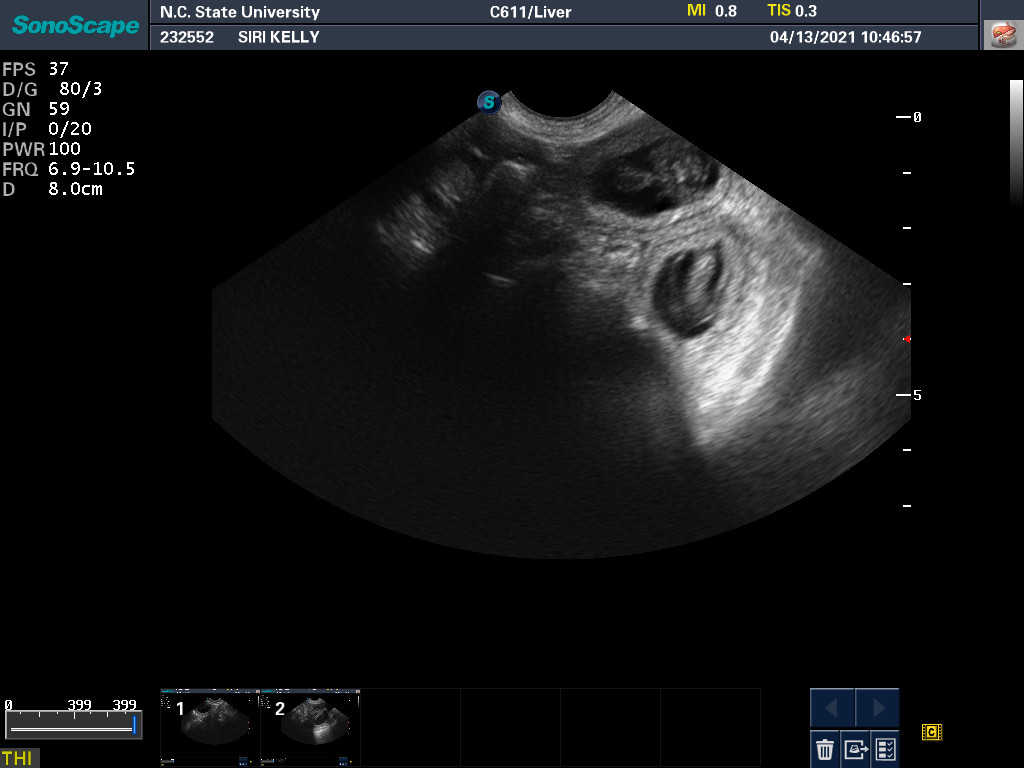

13 Apr

Ultrasound today by the theriogenology (reproduction) veterinarians at NC State University showed that Siri is pregnant with possibly four puppies. (It can be difficult to accurately count puppies using ultrasound.)

If all goes well, puppies are due around 18 May.